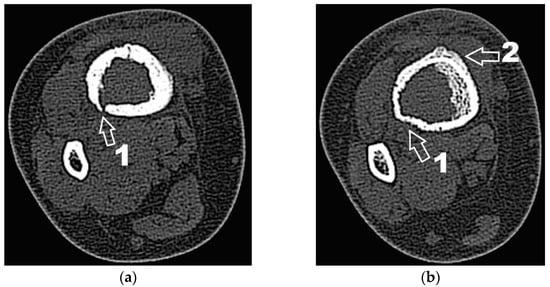

Next, the patient was investigated by radiology, computer tomography (CT) imaging and bone scintigraphy. Radiological examinations (Figure 2) and contrast-enhanced computed tomography (Iomeron) describe an osteolytic lesion located in the distal third of the right tibial shaft with dimensions of 37/22/16 mm, associating thinning of the cortex with minimal interruptions and periosteal reaction on the anterior and internal face of the tibia. Contrast-enhanced CT examination at the abdominal, thoracic and pelvic levels did not reveal any other lesions of the examined organs, except for a benign cyst located in the superior external quadrant of the left breast.

Figure 2. (a) Radiological image (coronal view); (b) Radiological image (lateral view). 1—osteolytic lesion; 2—periosteal reaction.